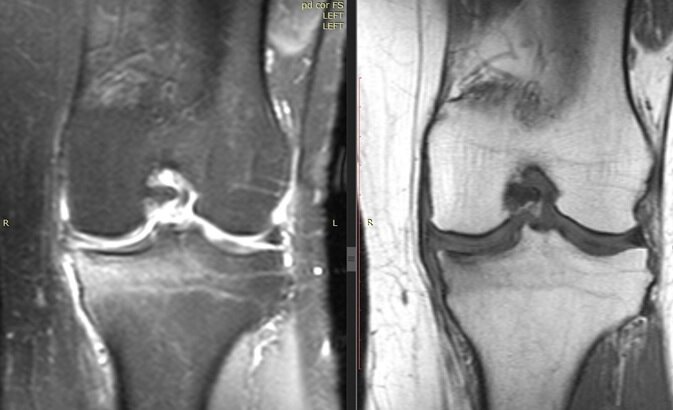

Что же было на МРТ у данной пациентки?

В описании и заключении МРТ четко звучал Диагноз: асептический некроз внутреннего мыщелка голени, разрыв мениска.

Наш совместный осмотр с врачом радиологом подтвердил то, что диагноз не верен.

Мы изменили диагноз на субхондральный перелом недостаточности внутреннего мыщелка большеберцовой кости, массивный субхондральный отек костного мозга внутреннего мыщелка больше берцовой кости, остеоартрит коленного сустава 2-3 степени, комбинированный разрыв мениска, острый болевой синдром. Надо сказать, что этот диагноз не намного прогностически лучше первого, но дает нам шанс попробовать справиться с болью без операции и сохранить сустав.

Наш результат через 2 мес подтвержденн данными МРТ.